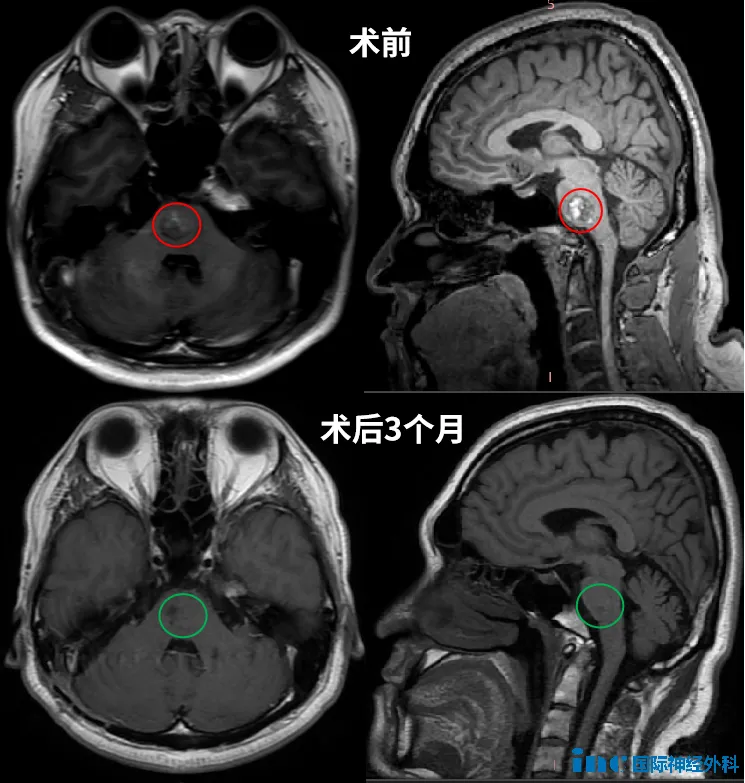

手术核心目标是在完全切除病灶的同时保护周围重要神经和血管。凭借精准术前规划和丰富临床经验,巴教授团队顺利开展手术。整个过程有序进行,每一步精准避开神经血管密集区,最终成功完整切除15×16×17mm病灶。

术后第一天患者清醒后,所有人员松了口气。其意识清晰,肢体活动完全正常,听力未受任何影响。

术前最担忧的面瘫、失聪等风险均未出现。曾经麻木无力的肢体在术后康复中逐渐恢复功能,日常生活逐步回归正轨。

术后1年4个月随访复查核磁显示完美结果:病灶完全切除,无残留、无复发。根据建议,杜先生下次MRI复查安排在2026年底,此后每三年复查一次即可。其无需特殊限制生活方式,可如正常人般生活,不再需要担忧脑桥海绵状血管瘤问题。